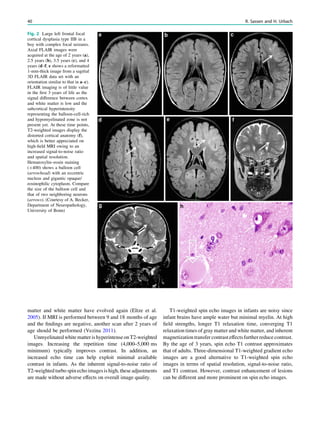

Fig. 2 Epileptogenic lesion and symptomatogenic zone. A 40-year-

old woman suffered from complex focal seizures with a fearful face

and body rocking. The symptoms thus pointed to the mesial frontal

lobe as the origin. MRI shows right-sided hippocampal sclerosis

(a, arrow). Simultaneous video and EEG recordings from interhemi-

spheric (c) and convexity strip and intrahippocampal depth (b) elec-

trodes show seizures starting in the right hippocampus (d, arrow).

Clinical symptoms start around 1 s afterwards (d, asterisk)